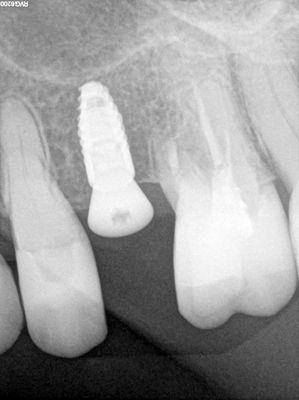

NSankhyan - immediate 13, impls 1121 and 25 with grafting

13 exo, loss of labial plate, implant placed buccal region grafted with sticky bone and collagen membrane soaked in prf fluid. 11/21 limited Labial-palatal width of bone, ridge split to 5mm, osteotomies prepared to about 2mm, remainder with densah drills, implants placed with ample bone, buccal grafted with same sticky bone. densah drills used for apical portion of 25 implant, soft bone, implant placed